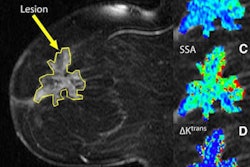

The study included 154 cases, consisting of normal, benign, and malignant lesions. The images came from a database of recalled women who had bilateral FFDM and DBT in the mediolateral-oblique (MLO) and craniocaudal (CC) views. Thirteen readers read the series of 154 cases twice, one month apart.

For the CC view, Michell's group found the overall area under the receiver operator characteristics curve (AUC) to be 0.78 for FFDM and 0.82 for DBT -- for a borderline statistically significant difference (p-value = 0.05) between the two modalities. As for the MLO view, however, the overall AUC was 0.83 for FFDM and 0.87 for DBT, which was not statistically significantly different (p-value = 0.129).